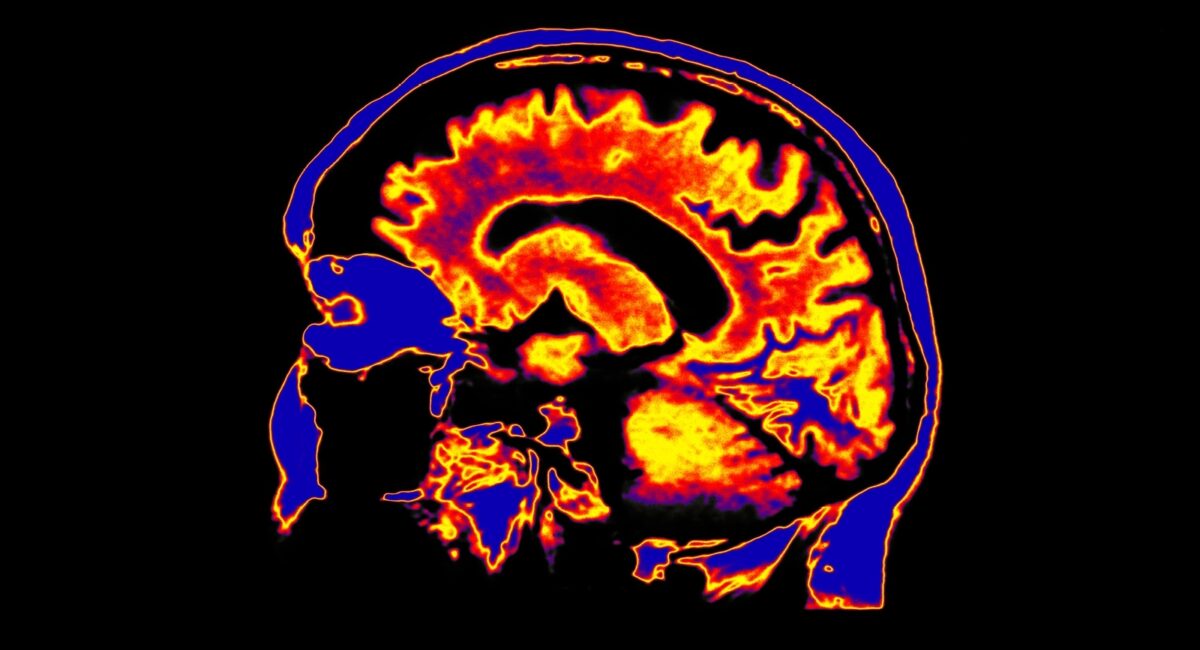

Functional Neurological Disorder (FND) is a problem with the functioning of the nervous system, i.e., how the body and brain send and receive signals.

This disconnect between brain and body reveals itself in a wide variety of distressing physical, sensory and cognitive symptoms, including numbness, limb weakness, chronic pain, tremors, and dissociative attacks that resemble epileptic seizures. Symptoms can be fleeting or last for years, and although FND is one of the most common outpatient neurological conditions in Scotland, stigma, lack of awareness and understanding about the condition means that it’s often difficult for sufferers to be diagnosed and receive treatment.